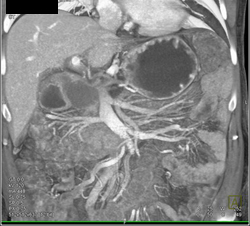

Pseudocyst